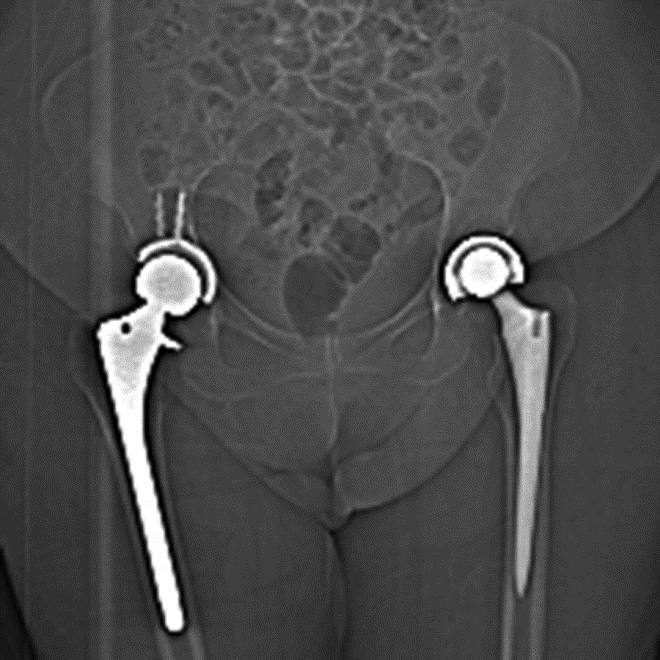

Complex cross-sectional geometry implants will result in streak artifact along the axes of greatest cross-sectional thickness (Buckwalter, 2011). In the presence of multiple implants the artifact will be most severe along the axis containing both implants. For example, with bilateral hip arthroplasties, the artifact will be most pronounced along the right-left axis as the beam travels through both implants (Figure 3). By orienting the hardware with shortest dimension of the implant perpendicular to the table, the amount of associated streak artifact will be reduced.

Figure 3A Figure 3B Figure 4A Figure 4B

Artifact summation Artifact summation Windowing Windowing

Artifact Summation. (A) Scout image demonstrates bilateral total hip arthroplasties. (B) Axial CT image at the level of acetabular cup and femoral head shows severe transverse streaking related to total summed attenuation of metal components. Optimal Windowing. (A) Axial CT image of the pelvis viewed in soft tissue windows demonstrates extensive streak artifact due to total hip arthroplasty prohibiting evaluation of adjacent bone and soft tissue structure. (B) Same axial CT image set to bone windows results in improved visibility of adjacent bone and soft tissue anatomy.